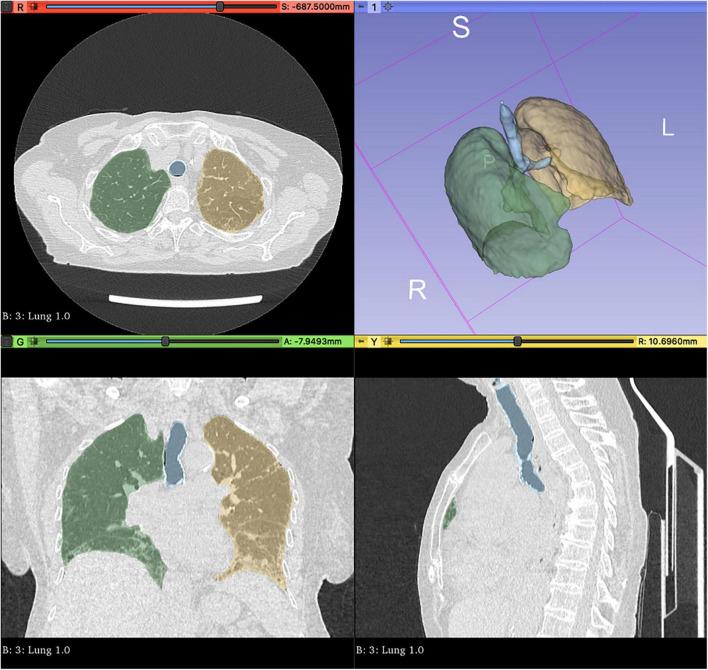

High-resolution computed tomographies of RA patients from January 2012 to March 2022 were analyzed. The time between the first available HRCT and the last follow-up visit or ILD-related death was recorded. We performed a volumetric analysis in 3D Slicer, automatically segmenting the whole lungs and trachea the Lung CT Analyzer. A LASSO-Cox model was carried out by considering ILD-related death as the outcome variable and extracting radiomic features as exposure variables.

方法